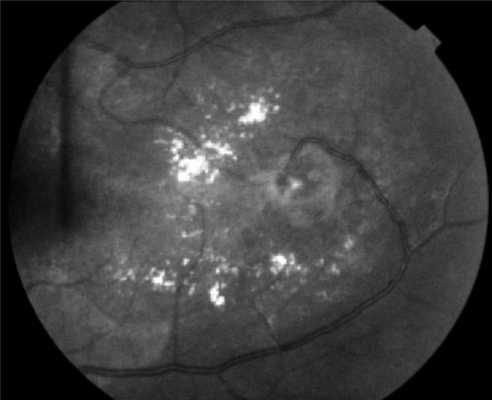

Поражения глаз выявляются примерно у 37% пациентов с VHL-синдромом, среди них только у 14% обнаруживается полная делеция VHL [51, 52]. Приблизительно у 8% пациентов снижена острота зрения [53]. Для лечения ангиомы сетчатки используют лазерную или криотерапию [32, 34, 54]. Недавние исследования [ 55, 56] показали, что при внутривенном введении антагониста сосудистого эндотелиального фактора роста (anti-VEGF) в течение 7 мес размер гемангиобластом не уменьшается (рис. 3). Рисунок 3. Ангиоматоз сетчатки.

Поражение глаз на ранних стадиях диагностируются лишь при офтальмоскопии. После 8 лет появляются жалобы на туманность изображения и его искажение (метаморфопсии). У половины пациентов выявляется поражение обоих глаз. Увеличивающиеся со временем ангиомы сетчатки приводят к расстройству кровообращения в ее сосудах, ишемии и кистозной дегенерации. В поздней стадии возможны увеит, катаракта, отслойка сетчатки, глаукома, гемофтальм.

Предполагать и исключать болезнь Гиппеля-Линдау следует в каждом случае выявления ангиоматоза сетчатки в ходе офтальмоскопии, особенно при наличии отягощенного семейного анамнеза. В начальной стадии офтальмоскопия может определять одиночную ангиому сетчатки с дилатацией питающих ее сосудов, впоследствии ангиомы становятся множественными, характерны аневризмы и змееобразная извитость сосудов. Диагностировать самые ранние изменения сосудов сетчатки и стертые формы позволяет флюоресцентная ангиография сетчатки. С ее помощью можно дифференцировать изменения сетчатки, сопровождающие болезнь Гиппеля-Линдау, от другой офтальмологической патологии: ретинопатий, ритинита, ретинобластомы, нейропатии зрительного нерва и пр. Уточнение диагноза возможно при помощи лазерной томографии сетчатки.